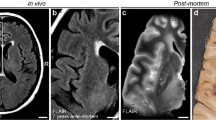

The first analysis of IVIM parameters focused on WMH manually delineated using the T2-FLAIR images and checked by the neuroradiologist (LW). Total WMH was calculated according to this segmentation. We assessed each IVIM parameter: the blood volume fraction, vbw, the bulk diffusion, D, the pseudodiffusion, D*, and the product vbw x D*, proportional to flow, voxel-wise throughout white matter segregated between regions of WMH, 4 mm thick peri-WMH zones, and remaining normal-appearing white matter (NAWM) (see Fig. 1 for an example). Peri-WMH zones were defined by dilating the segmented WMH regions by one voxel. All analyses were restricted to white matter for each patient using the white matter segmentation from preprocessing in SPM12. Differences in mean IVIM parameter values were assessed between regions for each patient. The mean difference between each pair of regions was evaluated by one-sample t-test across patients. A p < 0.05 was considered statistically significant after correction for multiple comparisons using false discovery rate.